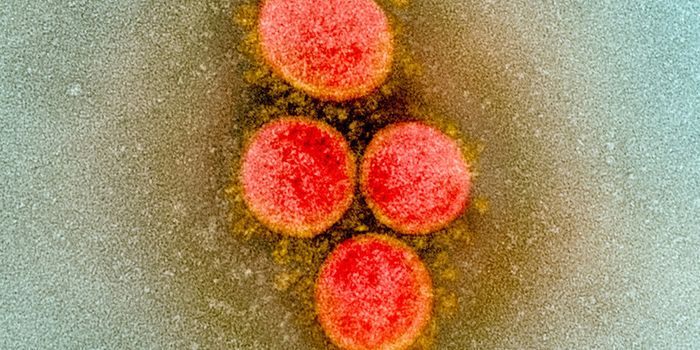

AUG 19, 2020Cell & Molecular BiologyAs the pandemic virus, SARS-CoV-2 continues to cause tens of thousands of new cases of COVID-19 every day in the United ...

FEB 08, 2020MicrobiologyIn China, authorities are still struggling to contain the new coronavirus that emerged in the city of Wuhan and has sinc ...

APR 27, 2020MicrobiologyThe pandemic virus that causes COVID-19 has now infected nearly 3 million people, and killed over 200,000.

MAY 10, 2021MicrobiologyThe pandemic virus SARS-CoV-2 has changed the world in devastating ways, taking hundreds of thousands of lives & new var ...

MAR 03, 2020MicrobiologyThere have now been nine deaths in the United States, all in Washington state from COVID-19, the illness caused by the n ...

MAR 10, 2020MicrobiologyThe vast majority (97.5%) of people will develop symptoms of infection within 11.5 days of exposure to the virus.

MAY 05, 2020Cell & Molecular BiologySamples obtained from patients from all over the world have been used to sequence the genomes of the viral strains infec ...

NOV 01, 2020MicrobiologySARS-CoV-2, which causes COVID-19 has to get into cells to cause infection. It does so with a spike protein on its surfa ...

FEB 15, 2021Cell & Molecular BiologyThe SARS-CoV-2 pandemic virus that causes COVID-19 has now had ample opportunity to infect millions, which has presented ...

SEP 23, 2020Cell & Molecular BiologyIn order to infect a cell, the SARS-CoV-2 virus has to find a way in. It can use receptors on the surface of cells that ...